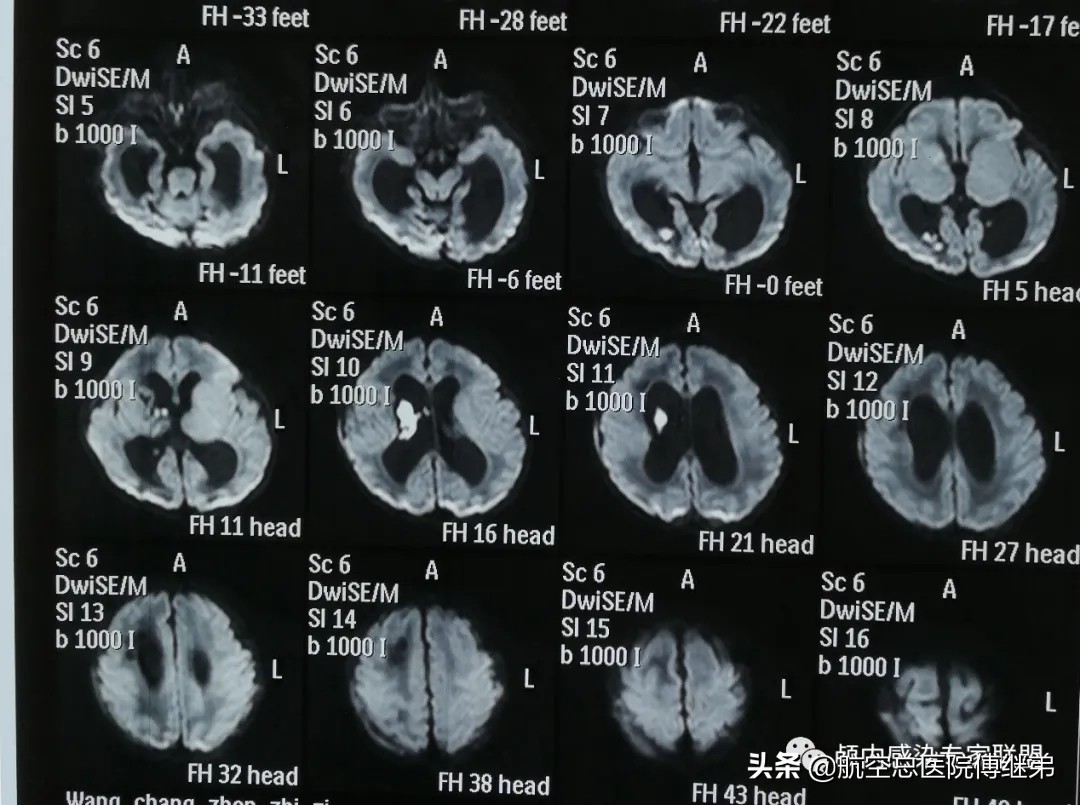

袁某,男,1岁,在孕检时就被诊断为先天性脑积水。因为当时患儿头围及发育未见明显异常,母亲就在足月后生出了这个外表健康的小宝宝,但患儿颅内的脑积水一直牵动着其父母的心。患儿出生后行颅脑MR检查可见颅内脑室系统扩张及脑出血(图一)。

图一:可见脑室系统扩张及右脑室内出血